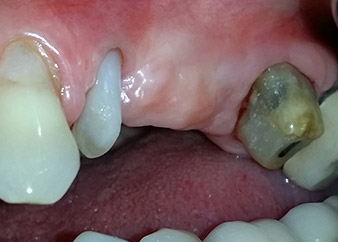

Ein Jahr zuvor waren die Zähne 25 und 26 vor dem Einsetzen der Brücke aufgrund traumatischer und endoparodontaler Ursachen extrahiert worden. Eine Paro-Endo-Läsion wurde bei unklarer ätiologischer Hauptkomponente für den Zahn 24 diagnostiziert. Die Patientin machte deutlich, dass sie ihre Pfeilerzähne 24 und 27 behalten und keinen endgültigen oder temporären herausnehmbaren Zahnersatz akzeptieren will. Darum wurde vereinbart, alles zu versuchen, beide Zähne, trotz der nach den radiologischen und klinischen Befunden als schlecht einzustufenden Prognose, zu erhalten.

Nach einer lokalen Applikation von 25-prozentigem Metronidazol-Gel (Elyzol) in die Taschen des Zahns 24 wurde die ursächliche Behandlung mit systematischer Parodontaltherapie einschließlich Full-Mouth-Disinfection begonnen. Die orthograde Wurzelkanalbehandlung wurde mittels einer thermoplastischen Obturation mit Guttapercha, einem Glasfaserstift und einem Komposit-Stumpfaufbau revidiert (Abb. 2). Die Brücke wurde außer Okklusion wieder befestigt, um die ungestörte Heilung der GTR- und GBR-Bereiche zu gewährleisten.